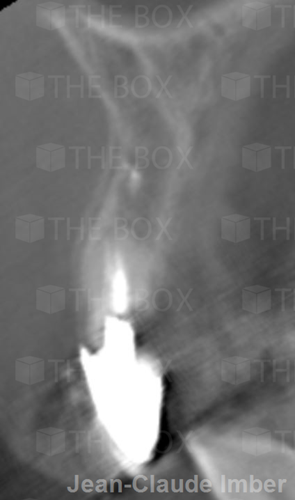

A new case was made public by Jean-Claude Imber check it out here.